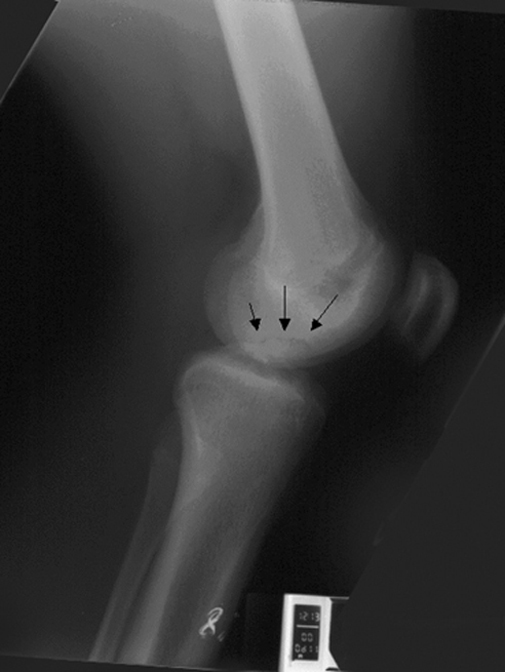

Диагностика остеохондрита коленного сустава на рентгене